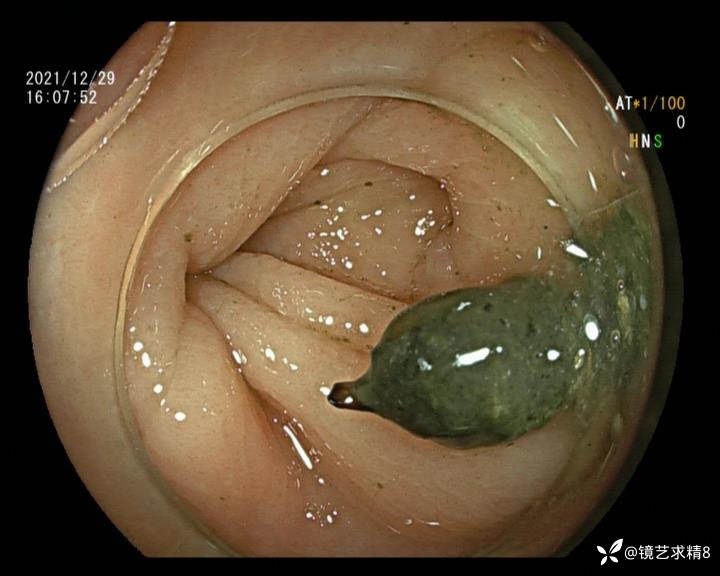

患者以消化道出血入院,胃镜未见异常,肠镜进入乙状结肠就看到很多憩室,同时还看到肠腔用清肠药后移动下来1枚尖锐的枣核,这么多憩室,这个枣核扎入憩室的机会非常大,推测应该是掉入一坑🕳就算出来还会有很多坑🕳🕳🕳等着,掉入憩室内很容易刺破血管,这可能就是消化道出血的原因,继续前进可以看到有一些憩室内翻,还有一些息肉,问题来了,那么多憩室,犯罪分子是抓住了,它在那些憩室内作过案?到达回盲部后挨个冲洗,但憩室大小又不足以把镜头进入憩室内观察,针对有血块的憩室冲洗后可疑出血的以夹子闭合或套扎,取出枣核,如果有锥形透明帽可能钻入憩室精准电凝效果更好,若内镜下操作失败介入治疗成功率更高,经内镜下治疗后观察未再出血出院。